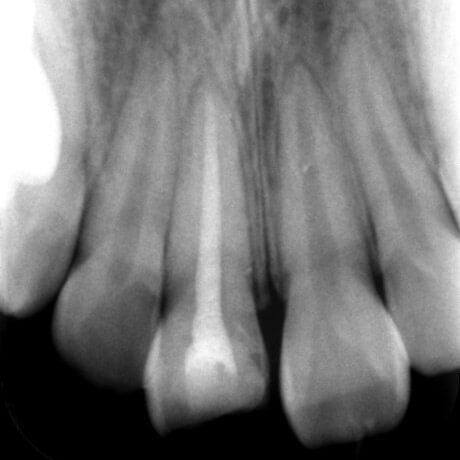

当日のレントゲンです。

神経治療のスタートのレントゲンです。

神経治療が終わった後のレントゲンです。